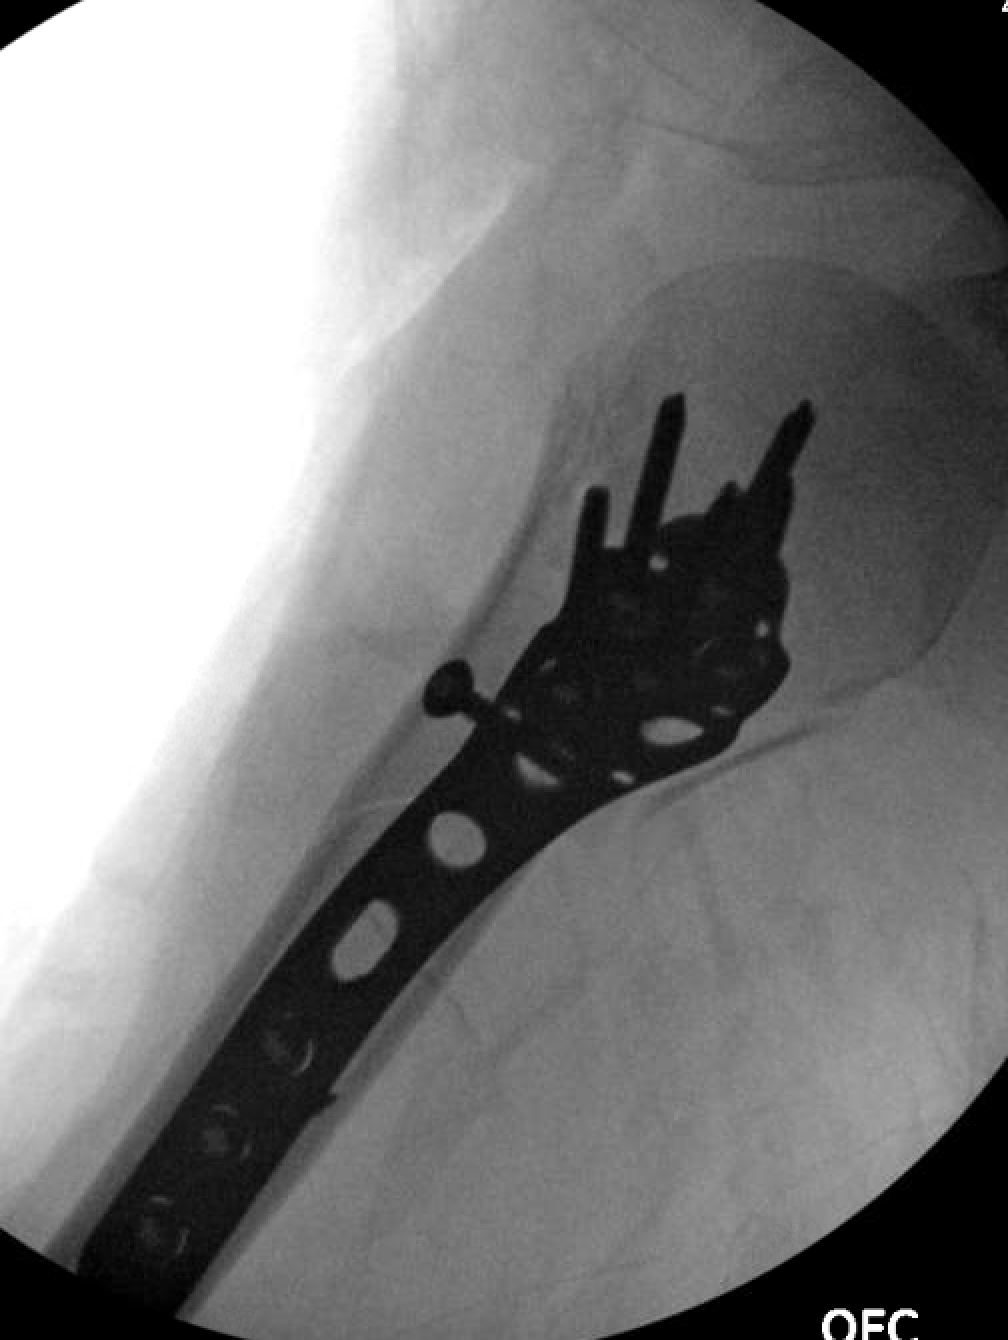

Postoperative images after the Eden Hybbinette are shown below: